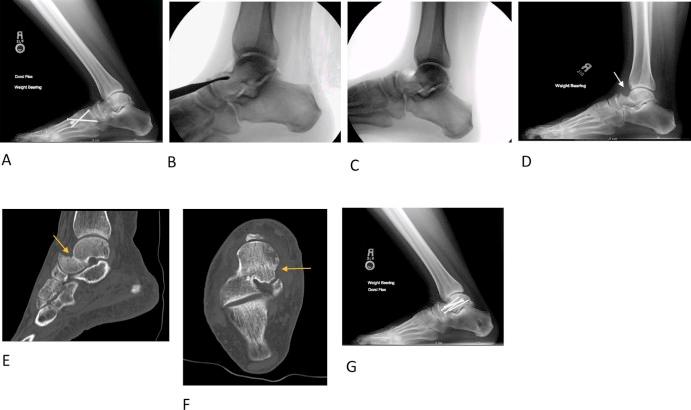

距骨不全骨折并发踝关节唇切除术

Talar insufficiency fracture complicating ankle cheilectomy.

Ankle cheilectomy as surgical treatment for anterior ankle impingement has high rates of procedural success and low rates of complications when performed before the onset of significant osteoarthritis. We present 3 patients who developed insufficiency fractures of the talar neck following cheilectomy for anterior ankle impingement. Due to the high risk of avascular necrosis associated with displaced talar neck fractures, the recognition of talar insufficiency fractures by the radiologist can aid in the timely diagnosis and initiation of intervention. Because radiographic findings of stress fractures often require weeks to manifest, maintaining a high index of suspicion in the postcheilectomy setting allows the radiologist to suggest appropriate further imaging when appropriate.

摘要

踝关节切骨术作为治疗前踝撞击症的手术方法,在严重骨关节炎发作前进行时,手术成功率高且并发症发生率低。我们报告3例因前踝撞击症行踝关节切骨术后发生距骨颈不全骨折的患者。由于移位的距骨颈骨折与缺血性坏死风险高相关,放射科医生识别距骨不全骨折有助于及时诊断并启动干预。因为应力性骨折的影像学表现通常需要数周才能显现,所以在踝关节切骨术后保持高度怀疑指数可使放射科医生在适当的时候建议进行适当的进一步影像学检查。